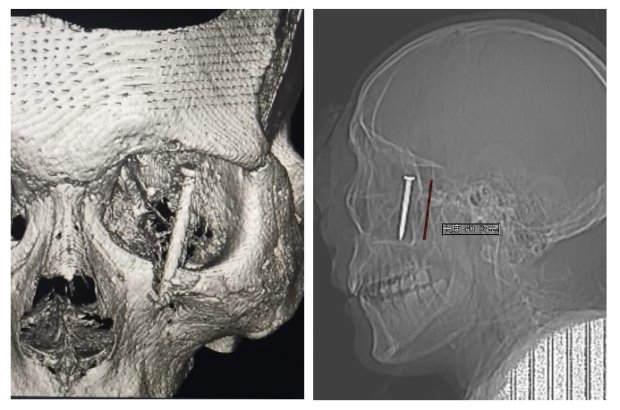

极速营救 | 4公分钢钉射入颅内,凶险!徐州一院多学科团队携手“拔”钉,漂亮!

在徐州市第一人民医院, 每一天都上演着生死时速的较量, 而这一次的挑战尤为艰巨。 一名中年男性在工作时不幸遭遇飞来横祸,一根长达4公分的钢钉猛然射入他的左眼,穿透眼球,...